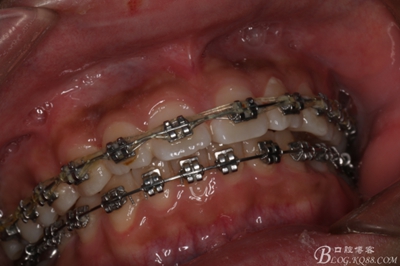

圖2.術(shù)前的口內(nèi)閉口位照片:上下牙列基本整齊

2_副本.jpg